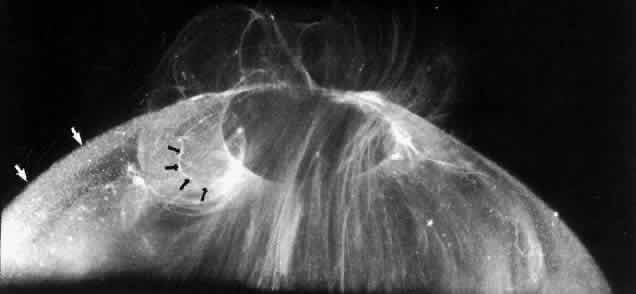

Fig. 14. The posterior vitreous is detached, and the prepapillary hole in the posterior vitreous cortex (arrows) can be seen anterior to the optic disc (slightly below and to the left of the optic disc) (Sebag J: The Vitreous--Structure, Function and Pathobiology. New York, Springer-Verlag, 1989)